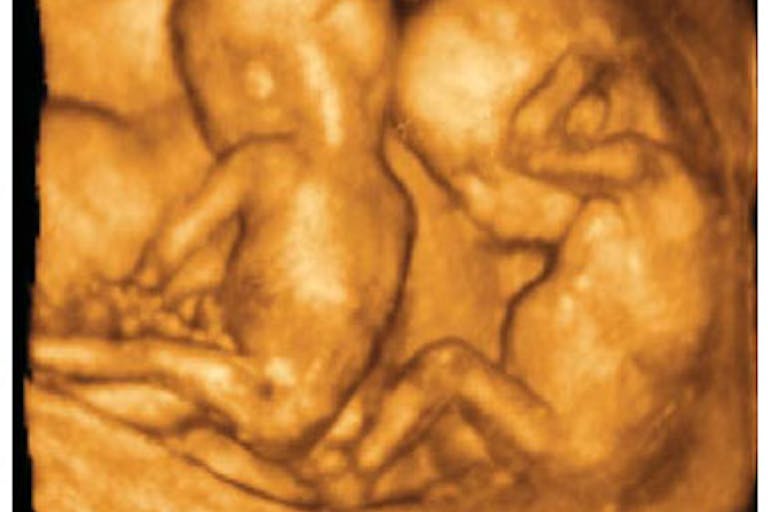

Joseph Barker and Luci Hall were thrilled to be expecting twins. The British couple’s excitement and joy soon turned to fear, however, when Hall went into early labor at just 24 weeks into her pregnancy. “When I went into labour, Joseph and I just weren’t prepared at all. It all happened so quickly,” she said. “It was so early and we were so worried about what was going to happen to them. We didn’t know if they were going to survive, it was terrifying. When they were born they were both rushed straight to intensive care, I didn’t get to hold them or see them.”

“I couldn’t even get upset about not getting to hold them because I was in shock. I couldn’t quite get my head around what was happening,” Hall said. “We got to see them three hours later and that’s when it really hit us. They were so tiny, you can’t even imagine a baby that small. It was really frightening.”

Both babies weighed barely over one pound each. And at first, doctors told Barker and Hall that their sons likely wouldn’t make it. “They told us not to think about the future because it was so uncertain,” she said. “We were so scared thinking about losing one of them or both of them, it was devastating. It’s not a situation you ever expect yourself to be in when you have your first baby.”

The boys, Charlie and Harvey, were struggling to survive, undergoing seven blood transfusions each and a bout of bronchiolitis. “We were watching our babies fighting for their lives. You can’t explain what it’s like to be in that situation, it’s horrendous. It’s like your worst nightmare, I felt so helpless,” she said. “All I wanted to do was hold them and comfort them but I couldn’t do anything. All I could do was be there every day.”

But instead of dying, the boys grew stronger every day. “They are both little fighters,” Hall said. “They proved everyone wrong.” Now, the 15-month-olds weigh over 20 pounds each, and are thriving. But their miraculous survival has their parents questioning how babies the same age as their sons were when they were born can be legally aborted.

“Seeing how well they’ve done does make you think about the abortion limit. I’d never even considered it before, I just accepted it,” she admitted. “Then the twins came and I saw them in their incubator and suddenly the idea of a baby being aborted at 24 weeks broke my heart. The thought of anyone getting rid of a baby that late is just awful. When I came home I signed a petition to have it changed.”

Abortion is legal in the United Kingdom until 24 weeks of pregnancy on healthy babies, but if the preborn child is diagnosed with a disability or birth defect, abortion can be committed at any time throughout the pregnancy. Some groups, such as the Royal College of Midwives, are petitioning to have the limit on abortion expanded, to allow abortion at any point throughout the pregnancy, for any reason.

But as Hall discovered, these are human beings, capable of life outside of the womb, and as medicine advances, the date of viability will surely become earlier and earlier in pregnancy — which proves the inherent humanity of these children.